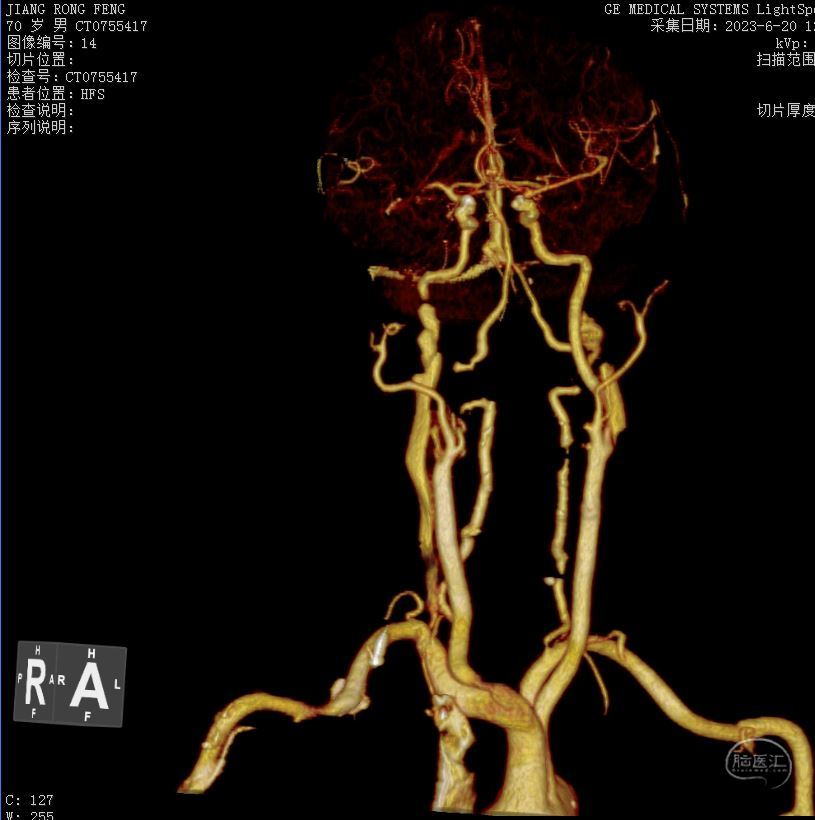

辅助检查:2023-6-20我院头颅CT及CTA示:右侧颈内动脉C1、C2段栓塞,右侧大脑中动脉M1、M2段栓塞,远端分支减少。右侧椎动脉V1段起始处狭窄;左侧C1段起始处狭窄。右侧额颞顶叶可疑稍低密度影。

入院急诊头颅及颈部血管CTA,提示多根血管病变,右侧责任血管串联病变可能。